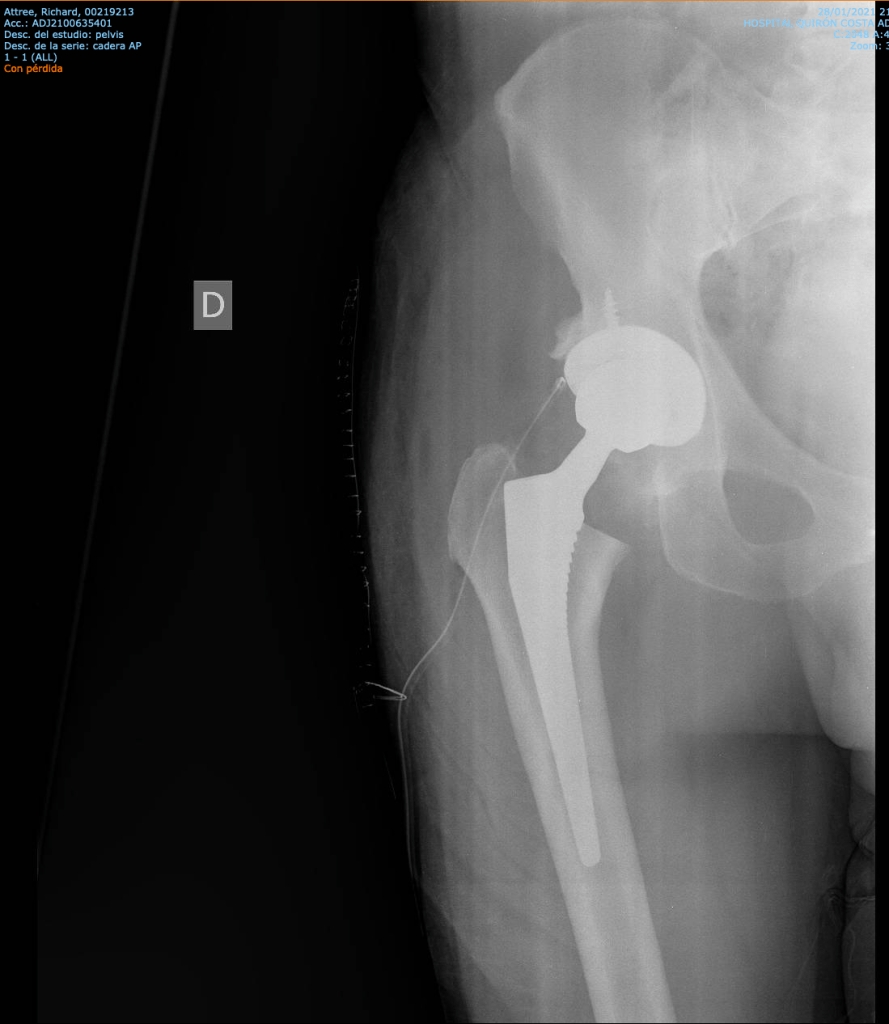

An hour after the op, I’m wheeled down to Radiography for the ‘after’ Xray. It must be OK, because it’s not mentioned again. Later, I download a copy—proof I’m now officially bionic. Hip, Hip, Hooray …